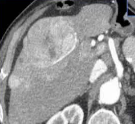

三、最关键结果(一句话总结)TARE 比 DEB-TACE 显著延长肿瘤进展时间,也显著延长总生存期,安全性相似。 在“经动脉放射性栓塞与化疗栓塞治疗肝细胞癌(TRACE)”试验中,随机分配至经动脉放射性栓塞(TARE)组或药物涂层栓子(DEB)经动脉化疗栓塞(TACE)组的参与者的疗效结果。Kaplan-Meier 图展示了(A)意向治疗组和(B)按方案组的总体肿瘤进展时间。P 值通过使用对数秩检验计算得出。虚线表示 95% 的置信区间。HR=风险比。